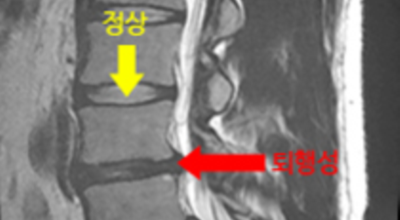

여러 개의 작은 척추뼈가 모여서 척추라는 인체의 기둥을 이루게 되어요. 척추뼈 사이에는 척추뼈끼리 부딪치는 것을 방지하는 쿠션 같은 역할을 하는 '디스크(disc)'라는 말랑말랑한 젤리 같은 구조물이 있는데 우리말로는 '추간판'이라고 하네요.

디스크(추간판)의 한가운데에는 젤리같이 찐득찐득한 '수핵'이라고 하는 성분이 들어 있어요. 그 주변에 수핵을 둘러싸는 '섬유륜'이라 하는 두꺼운 막이 있는데 디스크는 전체적으로 자동차의 타이어와 같은 형태라고 해요. 디스크는 일어선 상태에서는 중력을 받아 납작해져서 바깥쪽으로 약간 볼록한 형태가 된다고 해요.

디스크는 그 특수한 구조 때문에 웬만한 힘이 가해져도 효율적으로 쿠션 역할을 할 수 있겠습니다. 그러나 갑작스럽게 무거운 물건을 들어 올리거나, 부자연스러운 자세를 장시간 취하면 디스크에 무리한 힘이 가해지면서 디스크가 밖으로 돌출이 되게 돼요. 심한 경우 디스크를 감싼 막이 터지면서 그 안에 있는 수핵이 튀어나오게 돼요. 디스크는 대부분이 후방이나 후외방으로 돌출되는데 이 경우에 바로 곁에 있는 신경을 누르게 된다고 해요.